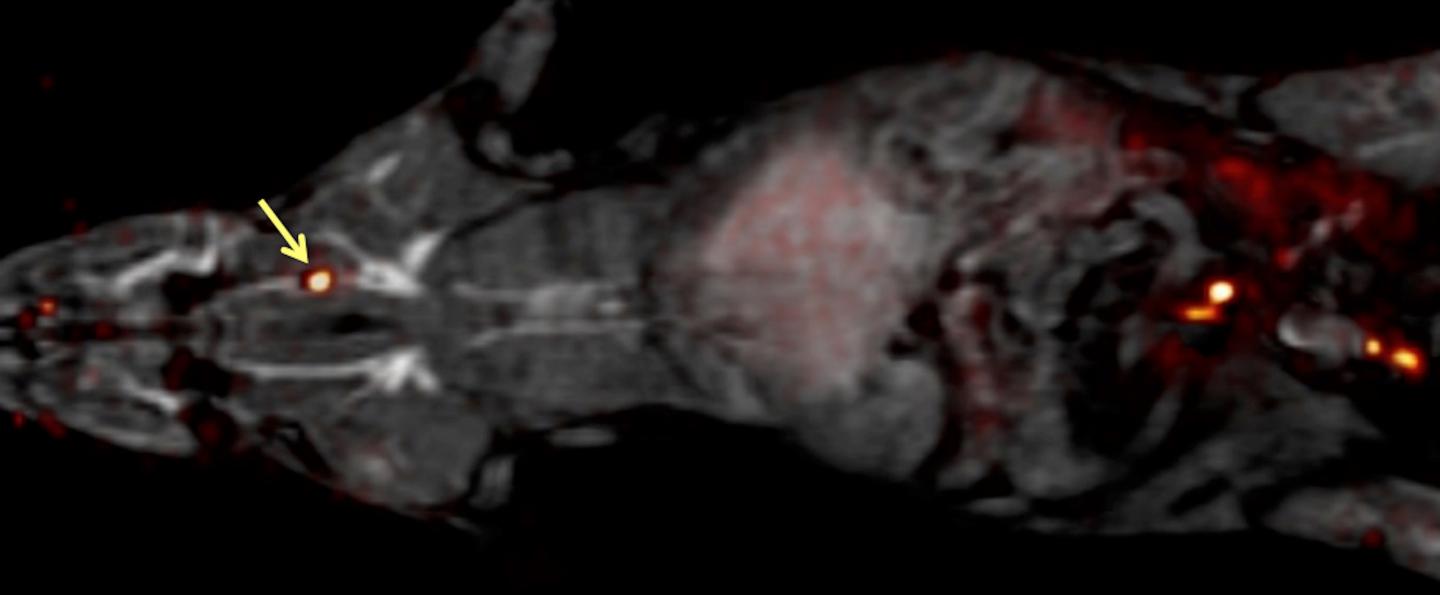

In previous work, Caravan's team at the Martinos Center for Biomedical Imaging at Massachusetts General Hospital identified a peptide that binds specifically to fibrin -- an insoluble protein fiber found in blood clots. In the current study, they developed a blood clot probe by attaching a radionuclide to the peptide. Radionuclides can be detected anywhere in the body by an imaging method called positron emission tomography (PET). The researchers used different radionuclides and peptides, as well as different chemical groups for linking the radionuclide to the peptide, to identify which combination would provide the brightest PET signal in blood clots. They ultimately constructed and tested 15 candidate blood clot probes.

The researchers first analyzed how well each probe bound to fibrin in a test tube, and then they studied how well the probe detected blood clots in rats. "The probes all had a similar affinity to fibrin in vitro, but, in rats, their performances were quite different," says Caravan. He attributed these differences to metabolism. Some probes were broken down quickly in the body and could no longer bind to blood clots, but others were resistant to metabolism. "The best probe was the one that was the most stable," he says. The team is moving forward into the next phase of research with this best-performing probe, called FBP8, which stands for "fibrin binding probe #8." It contained copper-64 as the radionuclide.